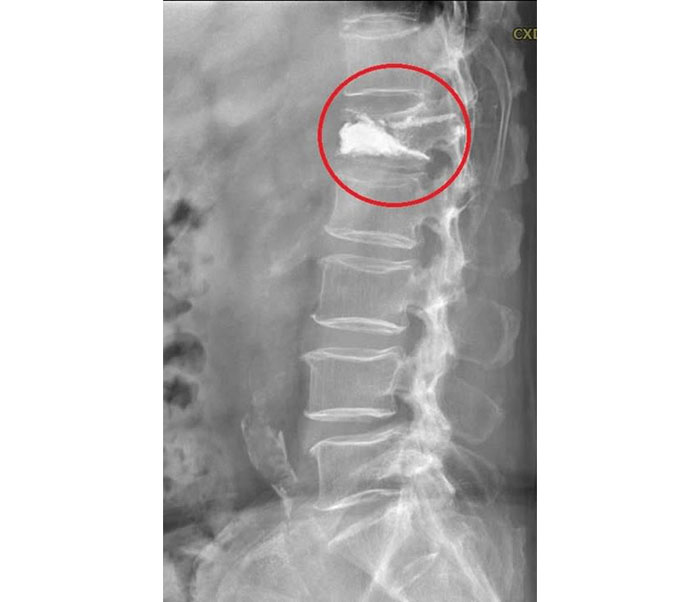

(优活健康网记者/王韵雅报导)77岁陈爷爷由于不明因素,导致背痛难耐,以为是背部拉伤的原因,但于诊所吃药复健都无法改善,遂至医院就诊。后续,神经外科医师透过影像及理学检查,发现陈爷爷腰椎第1节出现压迫性骨折,与家属讨论治疗方案后,决定执行“微创骨水泥手术”,术后隔日陈爷爷已能下床自行活动,恢复正常生活。

而针对严重压迫性骨折患者,则可选择进行“微创骨水泥手术”,透过3釐米的骨穿细针,再X光影像导引下将骨水泥注入椎体骨折处,除了可大大改善疼痛,术后可大幅增强椎体强度及脊椎稳定性。